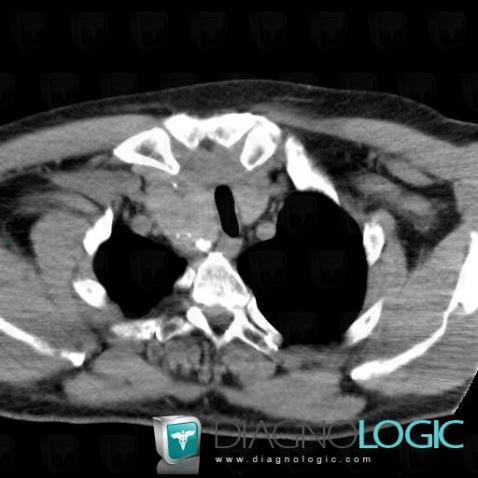

Goiter, Mediastinum, CT

Here is the specific information in the key image above:

- Diagnosis Goiter, Location(s) Mediastinum, with gamuts Superior mediastinal mass, Anterior mediastinal mass, Mediastinal mass with calcifications